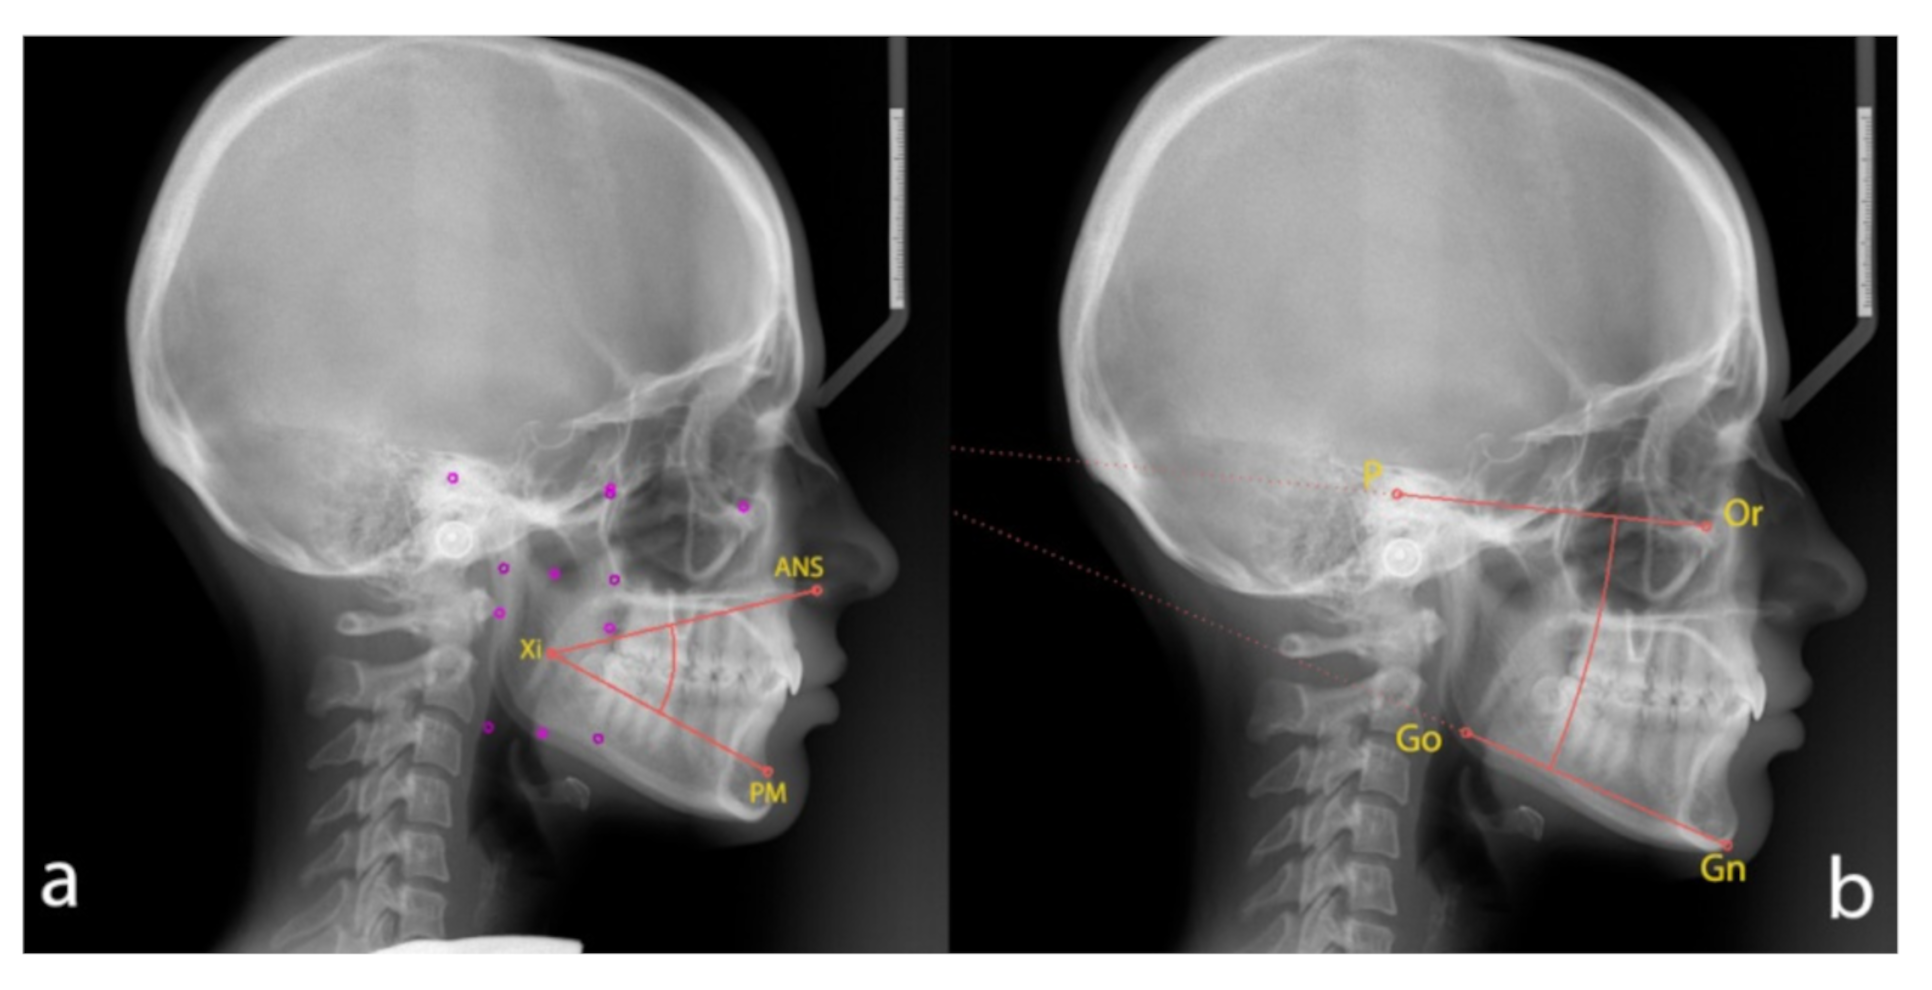

The following angles were measured for every subject (Figure 1):

Cephalometric analysis: (a) The lower facial height angle [LFHˆ], between anterior nasal spine [ANS], [Xi] point and prementon [PM]; (b) The angle [MLˆFH], between mandibular plane (gnathion [Gn]–gonion [Go]) and Frankfurt plane (porion [P]–orbitale [Or]).

- The lower facial height angle [LFHˆ], between [ANS], [Xi] point and [PM];

- The angle [MLˆFH], between mandibular plane (the plane tangent to the lower edge of the mandibular body, [Gn] and [Go]) and Frankfurt plane ([P] and [Or]).